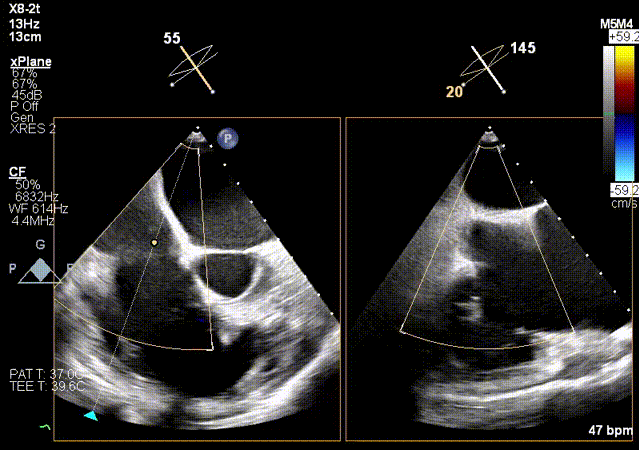

2.超声X-Plane以及实时3D下观察输送系统头端指向目标靶位。

X-Plane